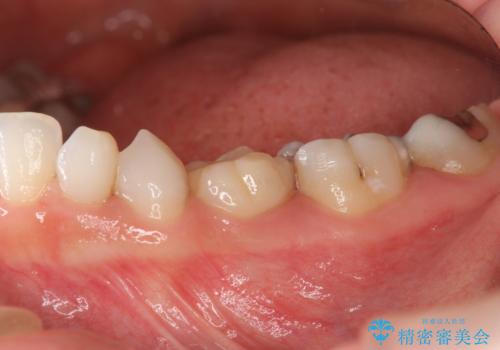

- 大人になっても残存していた乳歯がグラグラし、痛くて噛めない 抜いて欲しいとの希望で来院されました。

歯根が吸収し残すことのできない乳歯を抜去後、隣の歯を削らずに済むインプラント治療で咬合機能の回復を計画します。

乳歯の抜去後、インプラントを用いてしっかりと咬合機能を回復することができました。